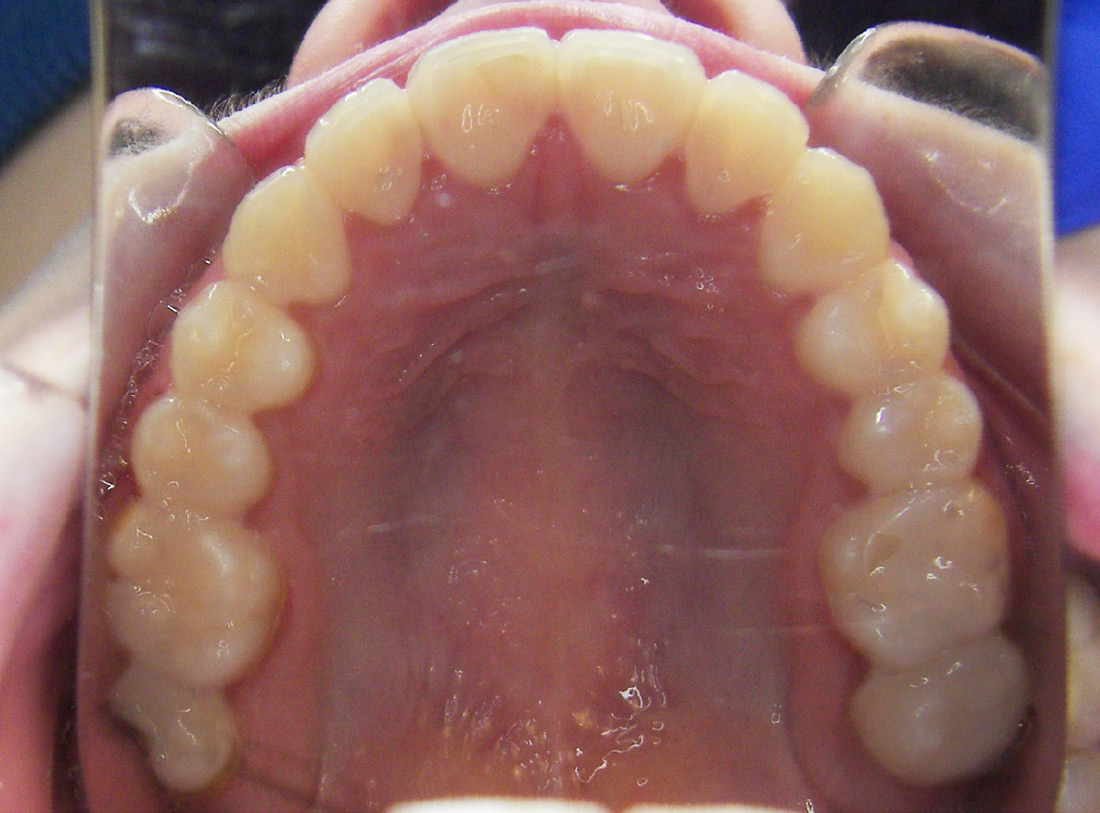

We’re proud of our patients’ new smiles, and most times, they’re even more proud to show them off. You’ll be ready for your close-up, too, once you visit the friendly experts at LB Orthodontics. Click here to see our smile gallery.